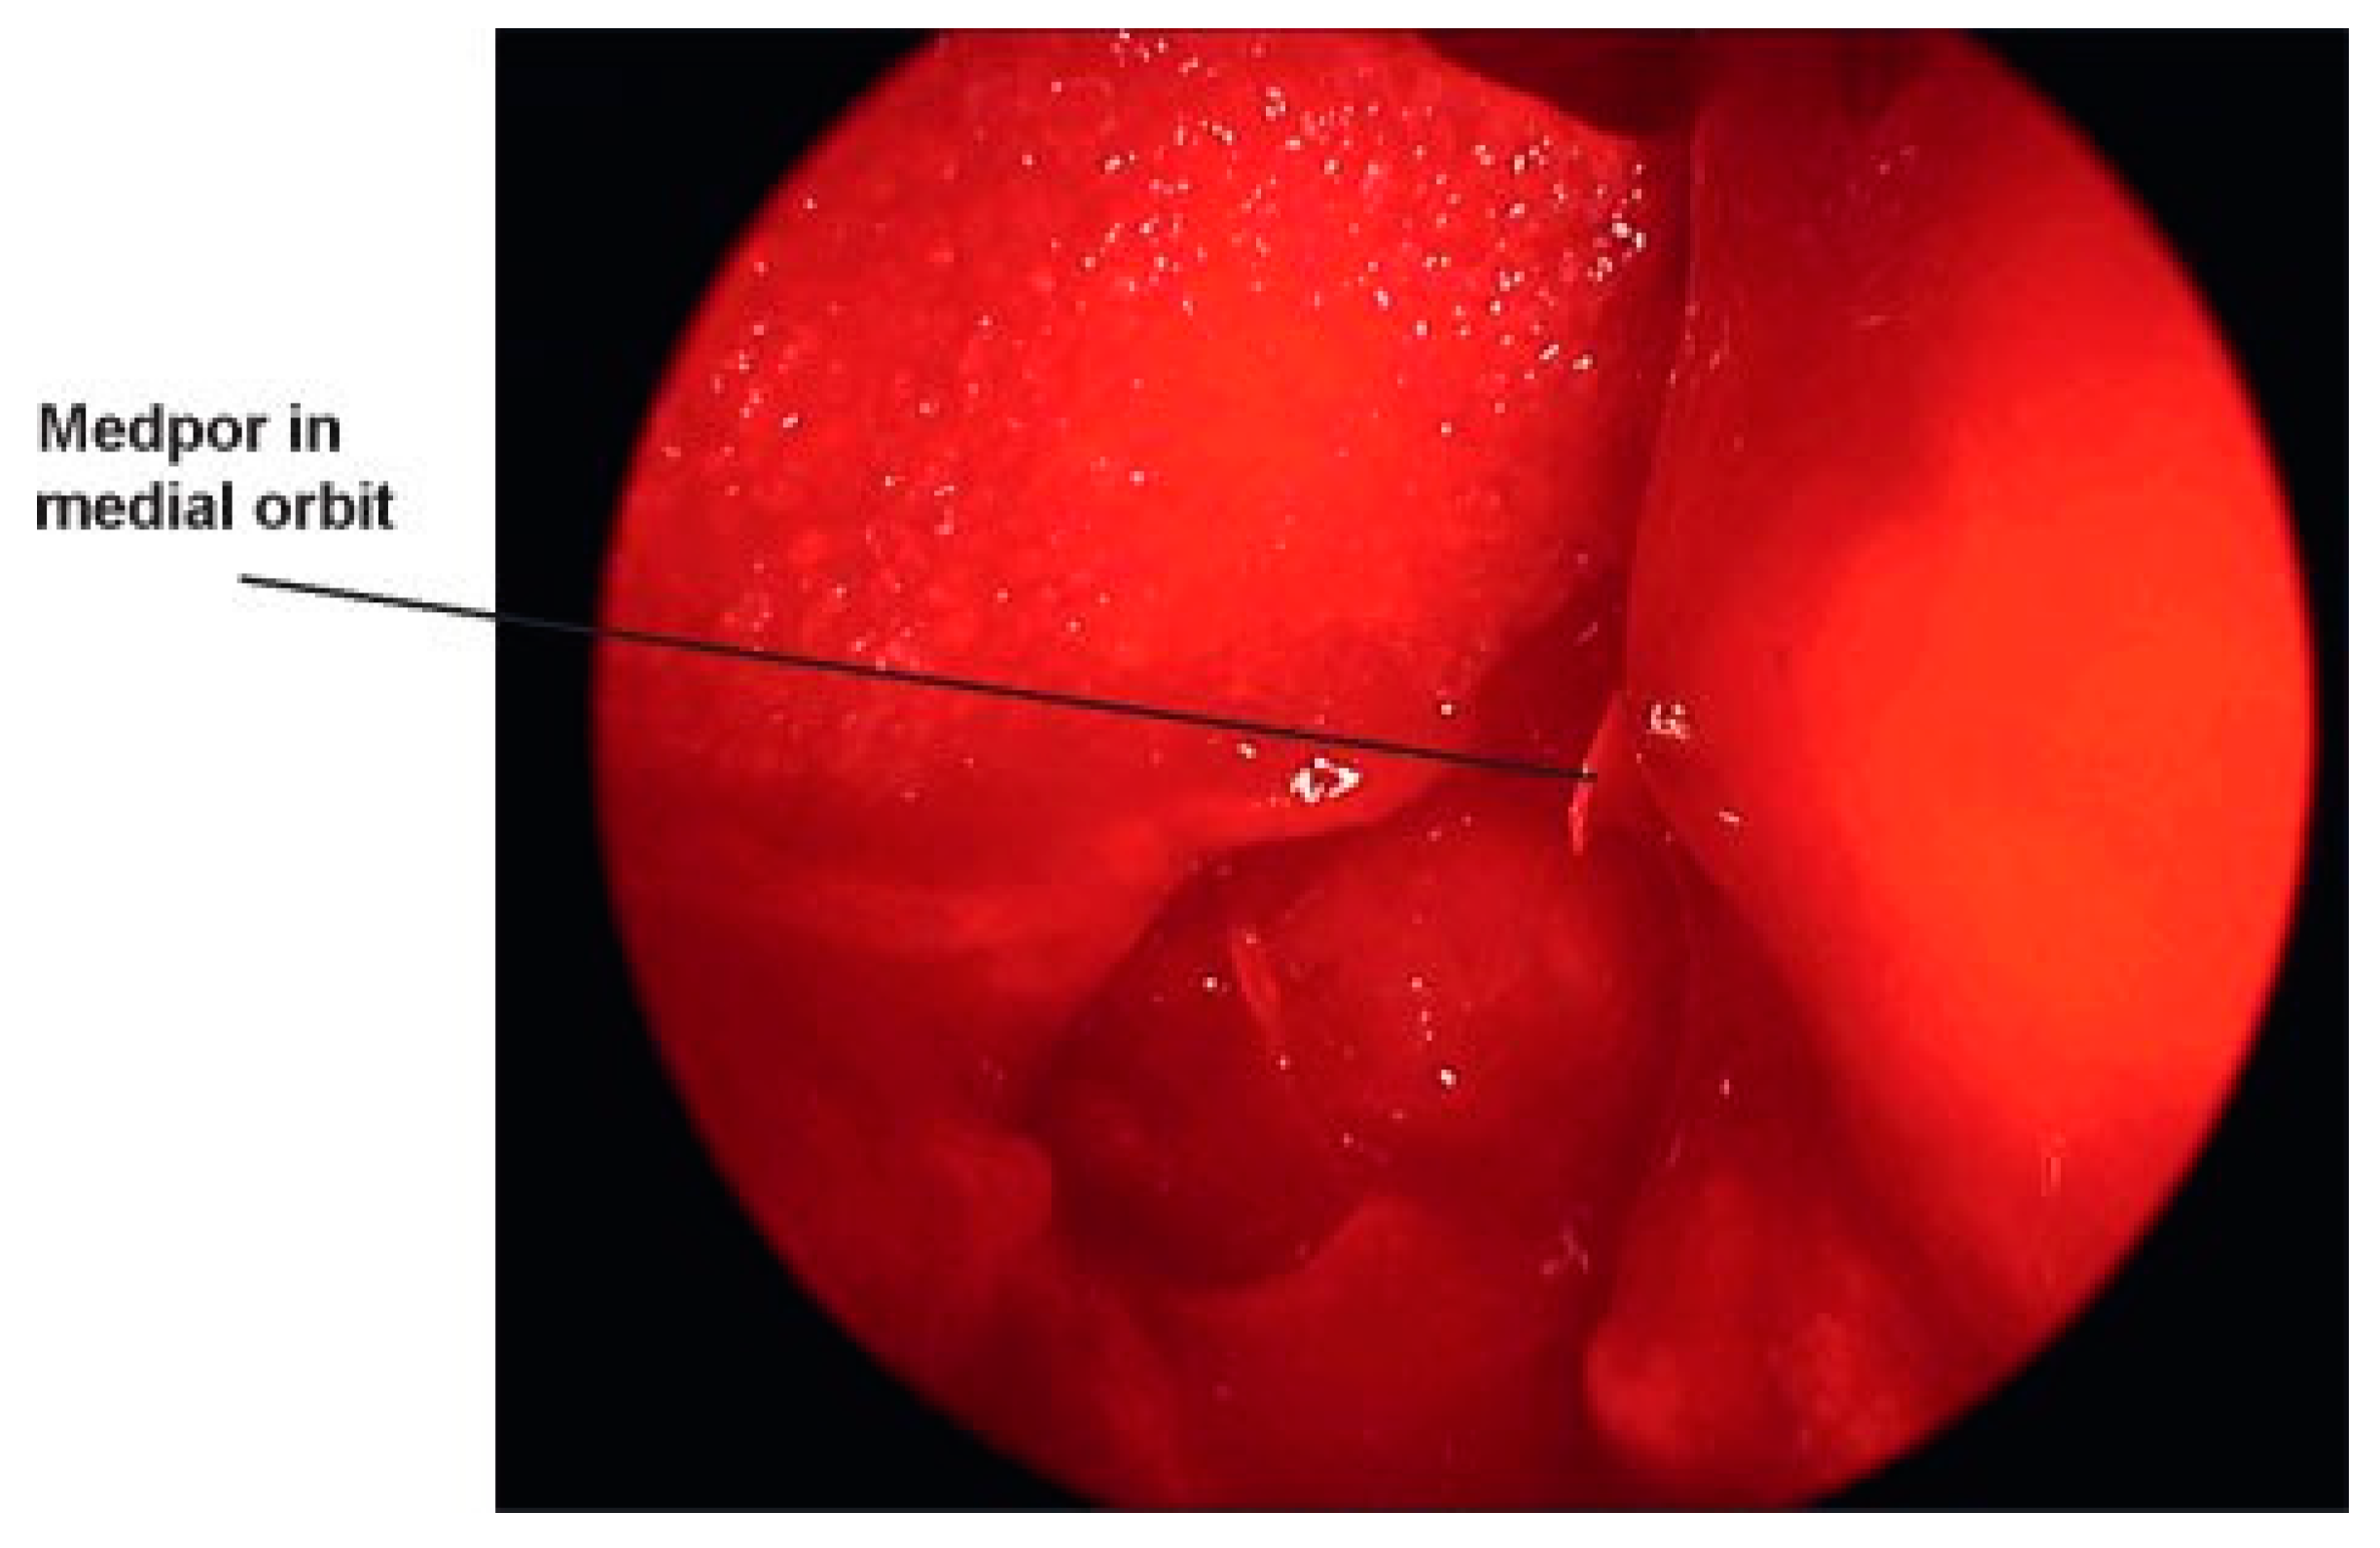

Medial orbital fractures are treated similarly to floor fractures except that these require more extensive knowledge of intranasal anatomy. To undertake the endoscopic repair, you must be aware of endoscopic skull base anatomy and be comfortable taking or medializing the middle turbinate and taking the uncinate process and ethmoid bulla down (Figure 8). If you can do this, you can have a full view of the lamina papyracea (Figure 9). Once the lamina is identified, you can ballot and find the defect. This is then most easily repaired with a Silastic sheet of sufficient stiffness to prevent herniation of the orbital contents. A thin Medpor sheet may also be used (Figure 10).

Figure 10. Medpor plate in place.